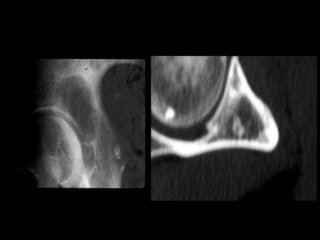

CT

• Good for evaluating cortical details and

destruction

• Subtle cortical erosions (endosteal;periosteal)

• not detectable on plain x-ray or MRI

• Subtle calcifications / ossification (Visible

tumor

matrix mineralization)